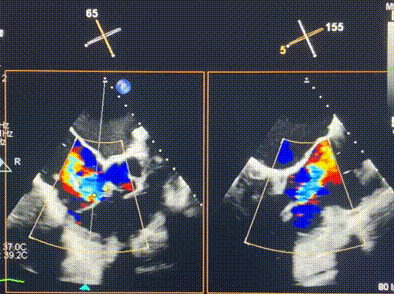

術(shù)前超聲提示重度三尖瓣反流

接受本次LuX-Valve Plus治療的是一位三尖瓣重度反流的高齡女性,患者早前曾由于二尖瓣疾病行經(jīng)導(dǎo)管二尖瓣置換術(shù),植入Tendyne瓣膜一枚,且有ICD植入史。術(shù)前CT分析結(jié)果顯示,瓣環(huán)大小為47.6mm,血管無(wú)明顯迂曲和鈣化。由于患者三尖瓣解剖結(jié)構(gòu)復(fù)雜,二尖瓣位人工瓣膜造成的超聲偽影和ICD導(dǎo)線的干擾使得歐洲沒(méi)有其他合適的商業(yè)化和臨床試驗(yàn)的產(chǎn)品可以對(duì)其進(jìn)行治療。經(jīng)過(guò)Rodrigo Estévez-Loureiro教授團(tuán)隊(duì)的詳盡術(shù)前評(píng)估,認(rèn)為L(zhǎng)uX-Valve Plus經(jīng)導(dǎo)管三尖瓣置換系統(tǒng)可以對(duì)該患者進(jìn)行有效的治療。因此,Rodrigo Estévez-Loureiro教授團(tuán)隊(duì)最終決定使用這一中國(guó)創(chuàng)新器械為患者進(jìn)行手術(shù)。法國(guó)波爾多里爾大學(xué)附屬醫(yī)院的Thomas Modine教授與加拿大圣保羅醫(yī)院的Anson Cheung教授全程線下指導(dǎo)本次手術(shù)。